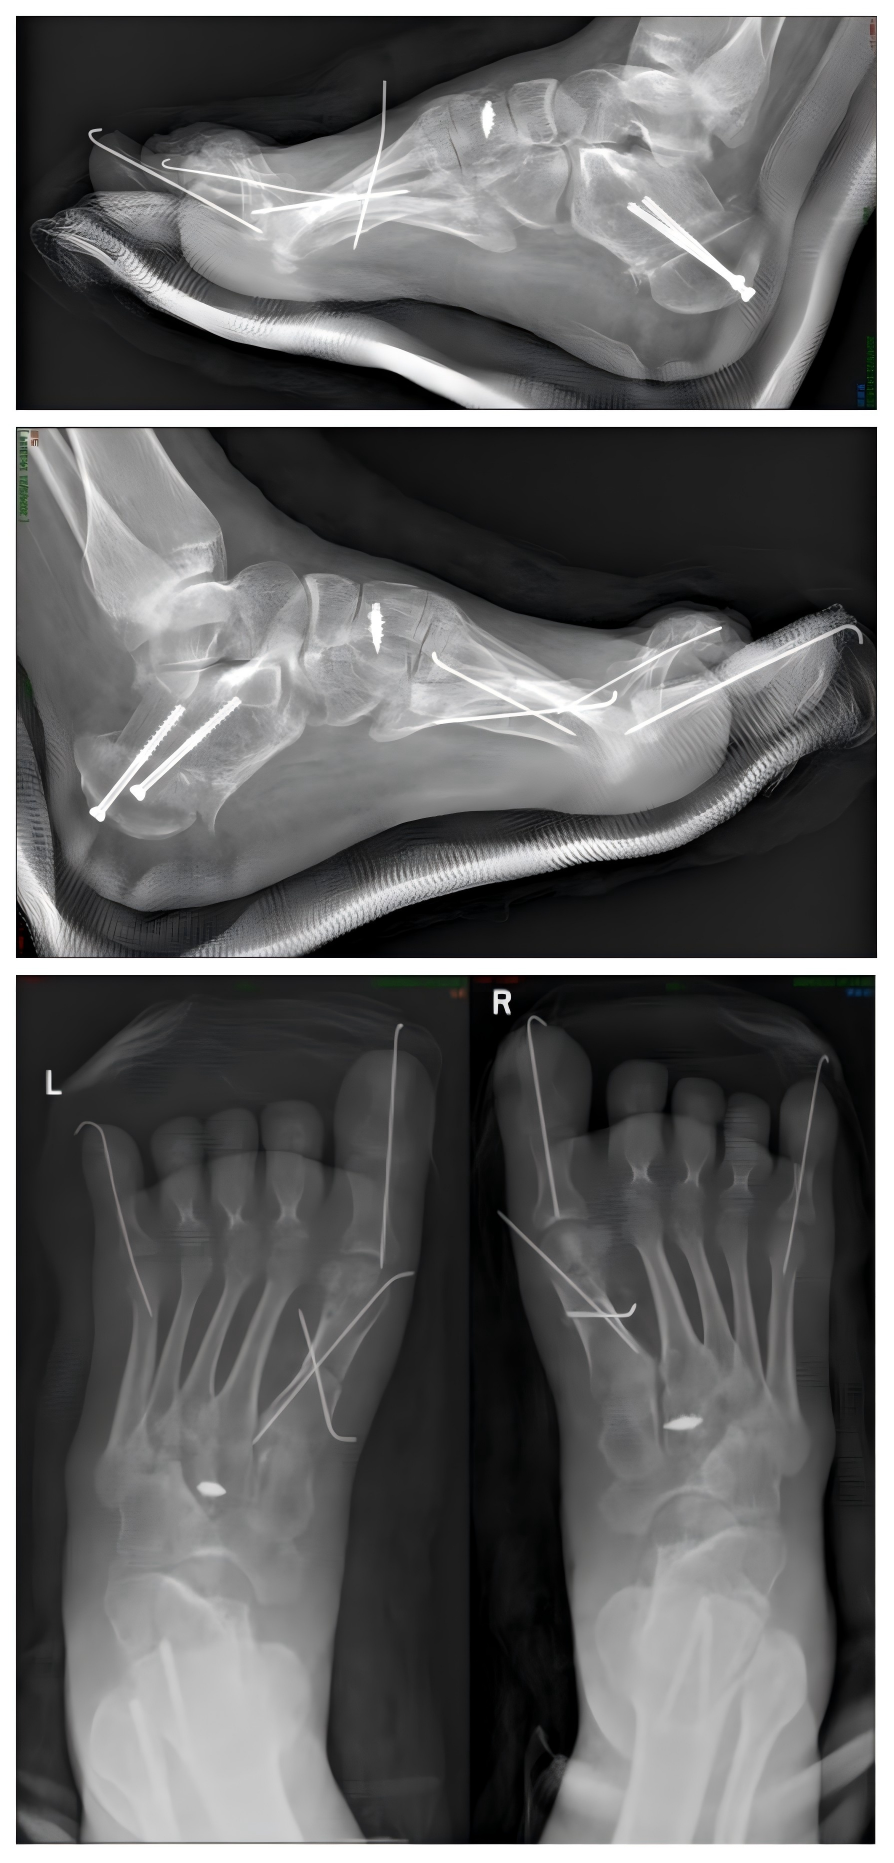

腓骨肌萎缩症是一种罕见病,2018年5月国家卫生健康委员会等五部门联合制定《第一批罕见病目录》中使用该名称。腓骨肌萎缩症主要是由于遗传因素出现下肢的渐进性活动性障碍,由于肌肉肌力的变化,导致足部及踝关节活动出现异常,手术治疗的原则是纠正足部畸形,重建和平衡足踝肌力。手术方案包括肌力平衡手术(各种类型的肌腱转移术)、软组织松解与矫形(足底筋膜切开术)、跟骨截骨矫形、腓肠肌复合体处理、踇趾矫形或其他足趾矫形手术。手术治疗有利于恢复患者的生活质量。